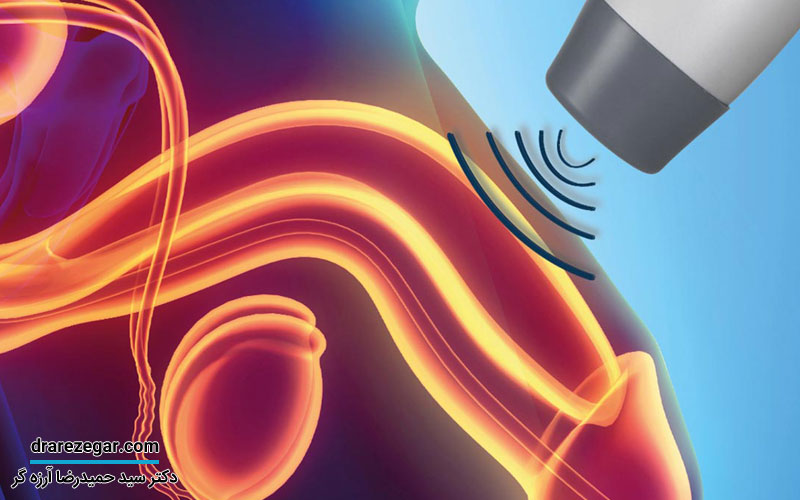

کسانی که با چنین علائمی همراه هستند؛ باید هرچه سریع تر توسط پزشک متخصص اورولوژی معاینه شوند تا علت آن تشخیص داده شود. سیستوگرافی، سونوگرافی، آزمایش ادرار و…چند نمونه از آزمایشات و تست هایی هستند که برای تشخیص این عارضه توسط متخصص اورولوژی انجام می شود.

• جراحی بسته پارگی مثانه: در بیشتر مواقع برای ترمیم و درمان پارگی های بخش خارجی صفاق، از کاتتر استفاده می شود. کاتتر یکی از انواع تجهیزات پزشکی است که معمولاً در جراحی هایی که به صورت بسته انجام می شوند؛ استفاده می شوند. برای انجام این جراحی، جراح کاتتر را برای 14 تا 21 روی بخش های پاره شده مثانه قرار می دهد تا ترمیم شود.